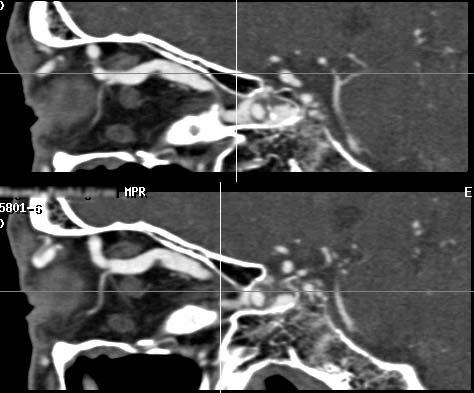

It has been a dream for radiologists to realize the "isotropic voxel" in CT where resolution is the same in x-, y- and z-axis since it will totally eliminate the partial volume averaging effect due to slice thickness. Half millimeter slices provides a true isotropic voxel in 24-cm field of view (FOV) and provides near-isotropic voxels in an 18-cm FOV (see Isotropic voxel). This means that the resolution of coronal and sagittal section is the same as that of an axial slice as shown in our clinical examples. Similar improvement can be observed in body-CT diagnosis with the use of 1-mm slices. I personally believe that this represents evolutional progress not only for CT diagnosis but also for all the slice-based diagnostic modalities.

As for the comparison of image characteristics of CT and MRI, it is believed that MRI is characterized by it's superb contrast resolution. However, it is a standard feature for current MRI units to provide slab thickness of 1-mm or less (e.g. MR angiography of the head using 3D-SPGR sequence, or CISS sequence for MR cisternography). Computed tomography, which is believed to be characterized by it's speed and superior spatial resolution, should be superior than MRI in terms of z-axis spatial resolution (slice thickness), otherwise CT examination may have little value in various clinical situations. This is especially true in the diagnosis of neuroradiological diseases, in which detailed interpretation of smaller anatomy is required.